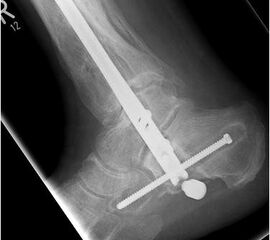

Durch die Fusion des oberen und unteren Sprunggelenkes soll eine Schmerzfreiheit bei gleichzeitiger Stabilität und Belastbarkeit in den genannten Gelenkabschnitten erreicht werden. Die Mobilität des Patienten bleibt damit gewährleistet. Durch Resektion der Gelenkflächen im OSG und im USG kann die Achse im Sprunggelenk korrigiert werden 67. Die Retention erfolgt durch einen von plantar aus eingebrachten Verriegelungsnagel. Orthopädietechnische Schuhzurichtungen oder sogar die Anpassung von orthopädischen Massschuhen sind nach einer Versteifungsoperation im OSG und USG häufig sinnvoll.

Von plantar aus nun Incision und Vorschießen eines 3er KDs durch Calcaneus, Talus bis in den Tibiaschaft hinein. BV-Kontrolle in beiden Ebenen. Bei korrekter Lage nun Eröffnungsbohrung. Wechsel auf einen Draht mit Olive. BV-Kontrolle in beiden Ebenen. Über den stumpfen Draht nun Aufbohren mit flexiblen Bohrern. Der letzte Bohrerdurchmesser sollte den Durchmesser des Arthrodesenagels um mindestens einen Millimeter übersteigen.

Implantation des Nagels und BV-Kontrolle (Video 5). Schließlich erfolgt die Verriegelung des Nagels über entsprechende Zielvorrichtungen. Bei einigen Nageltypen gibt es nageleigene Kompressionsmechanismen, die eine zusätzliche Drucksteigerung im Bereich der Arthrodeseflächen des ehemaligen oberen und unteren Sprunggelenkes erlauben (Video 6). Die abschließende BV-Kontrolle in beiden Ebenen sollte eine regelrechte Stellung der Arthrodese mit 90° - Stellung im Rückfuß, in der anderen Ebene mit einem Rückfußvalgus von ungefähr 5° zeigen.